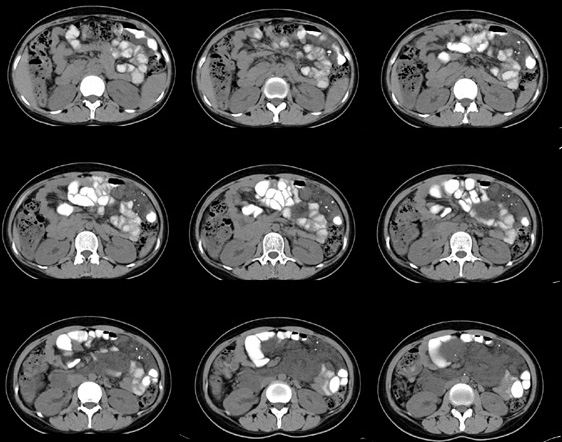

女性,28岁,停经3月,腹部膨隆1月,产前检查发现腹部占位

{肿块中心ct值27hu,增强后,动脉期、门脉期均无明显强化)

继续发

1 肠系膜肿块诸期无明显强化,肠系膜血管包绕其中但其周围仍见脂肪称“脂肪环征”;2 肠系膜血管远端较近端细,于重组像上见血管周围有强化结节为炎性结节,3肿块内见部分脂肪密度及少许点状钙化。4 腹膜后无肿大ln。

患者手术病理:腹腔囊性淋巴管瘤,象这样充满整个腹腔的的确很少见